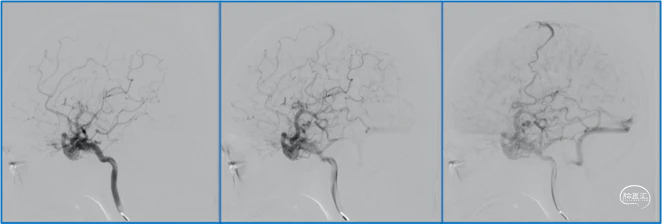

典型病例

稳妥的外科治疗方案:先介入栓塞颈外动脉的供血动脉,然后显微手术切断颈内动脉的供血动脉,阻断引流静脉,电凝封闭硬膜瘘口。

神经内镜可以辅助确认颞极深部的引流静脉,避免残留引流静脉。